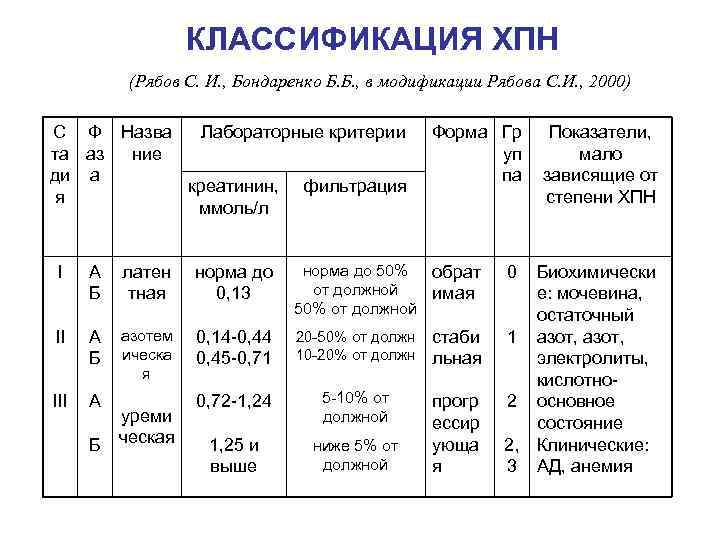

КЛАССИФИКАЦИЯ ХПН (Рябов С. И. , Бондаренко Б. Б. , в модификации Рябова С. И. , 2000) С Ф Назва Лабораторные критерии та аз ние ди а креатинин, фильтрация я ммоль/л Форма Гр уп па I А Б латен тная норма до 0, 13 норма до 50% обрат от должной имая 50% от должной II А Б азотем ическа я 0, 14 -0, 44 0, 45 -0, 71 20 -50% от должн 10 -20% от должн стаби льная III А 0, 72 -1, 24 5 -10% от должной 1, 25 и выше ниже 5% от должной прогр ессир ующа я Б уреми ческая 0 Показатели, мало зависящие от степени ХПН Биохимически е: мочевина, остаточный 1 азот, электролиты, кислотно 2 основное состояние 2, Клинические: 3 АД, анемия

КЛАССИФИКАЦИЯ ХПН (Рябов С. И. , Бондаренко Б. Б. , в модификации Рябова С. И. , 2000) С Ф Назва Лабораторные критерии та аз ние ди а креатинин, фильтрация я ммоль/л Форма Гр уп па I А Б латен тная норма до 0, 13 норма до 50% обрат от должной имая 50% от должной II А Б азотем ическа я 0, 14 -0, 44 0, 45 -0, 71 20 -50% от должн 10 -20% от должн стаби льная III А 0, 72 -1, 24 5 -10% от должной 1, 25 и выше ниже 5% от должной прогр ессир ующа я Б уреми ческая 0 Показатели, мало зависящие от степени ХПН Биохимически е: мочевина, остаточный 1 азот, электролиты, кислотно 2 основное состояние 2, Клинические: 3 АД, анемия